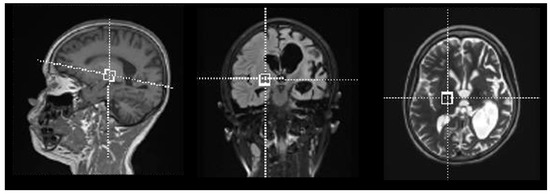

4.3. Data Acquisition